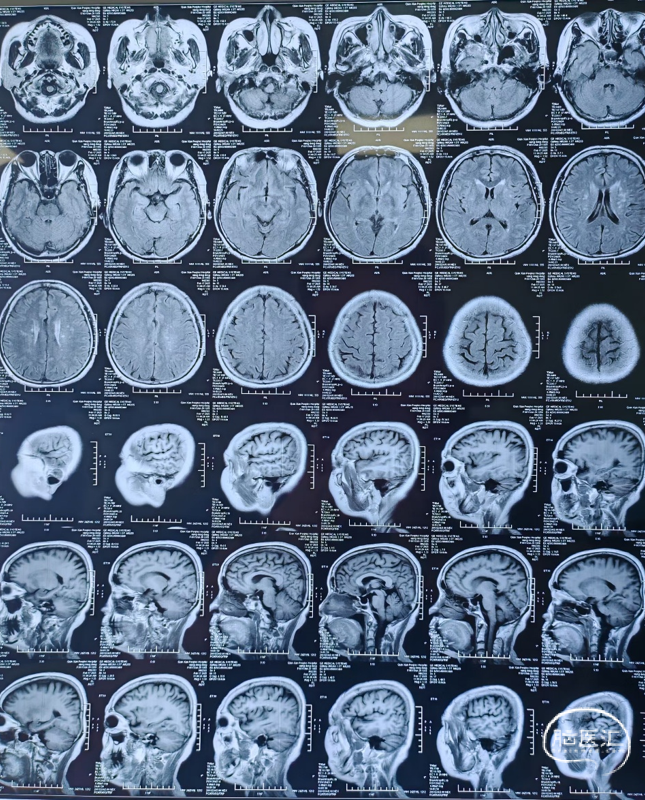

颅脑MRI+MRA

术前DSA